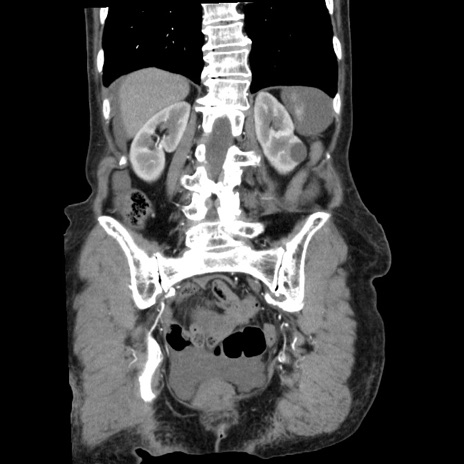

症例1(冠状断像)

【症例】80歳代女性

【主訴】腹痛

【現病歴】8時間前から腹痛あり来院。

【既往歴】糖尿病、脂質異常症、子宮体癌にて子宮全摘術

【身体所見】意識清明・会話良好だが腹痛で苦悶様、全腹部にわたって反跳痛と圧痛あり

【データ】WBC 13600、CRP 0.14、LDH 224、CK 90